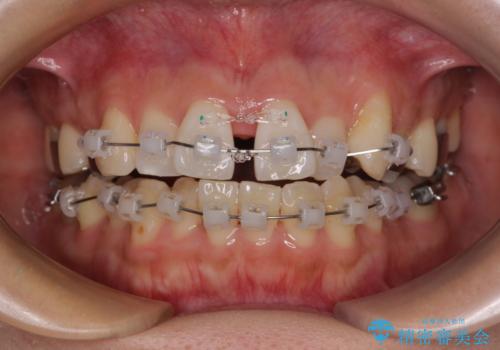

- クリアブラケット

- 1年3ヶ月

- 上下前歯のデコボコを気にして来院された患者様です。

上顎歯列が下顎の歯列に対して狭小であり、一部下顎の奥歯が上顎よりも外側に位置している状態でした。

上顎の急速拡大装置を使用して上顎骨を側方に拡大することで上顎歯列を拡大し、下顎歯列も拡大できるようにすることで、歯列を整えることとしました。

上顎の拡大は、左右どちらに拡大していくのか予想が困難ですが、こちらの患者様では結果として上下正中が一致する方向に拡大され、非常にきれいな仕上がりとなりました。